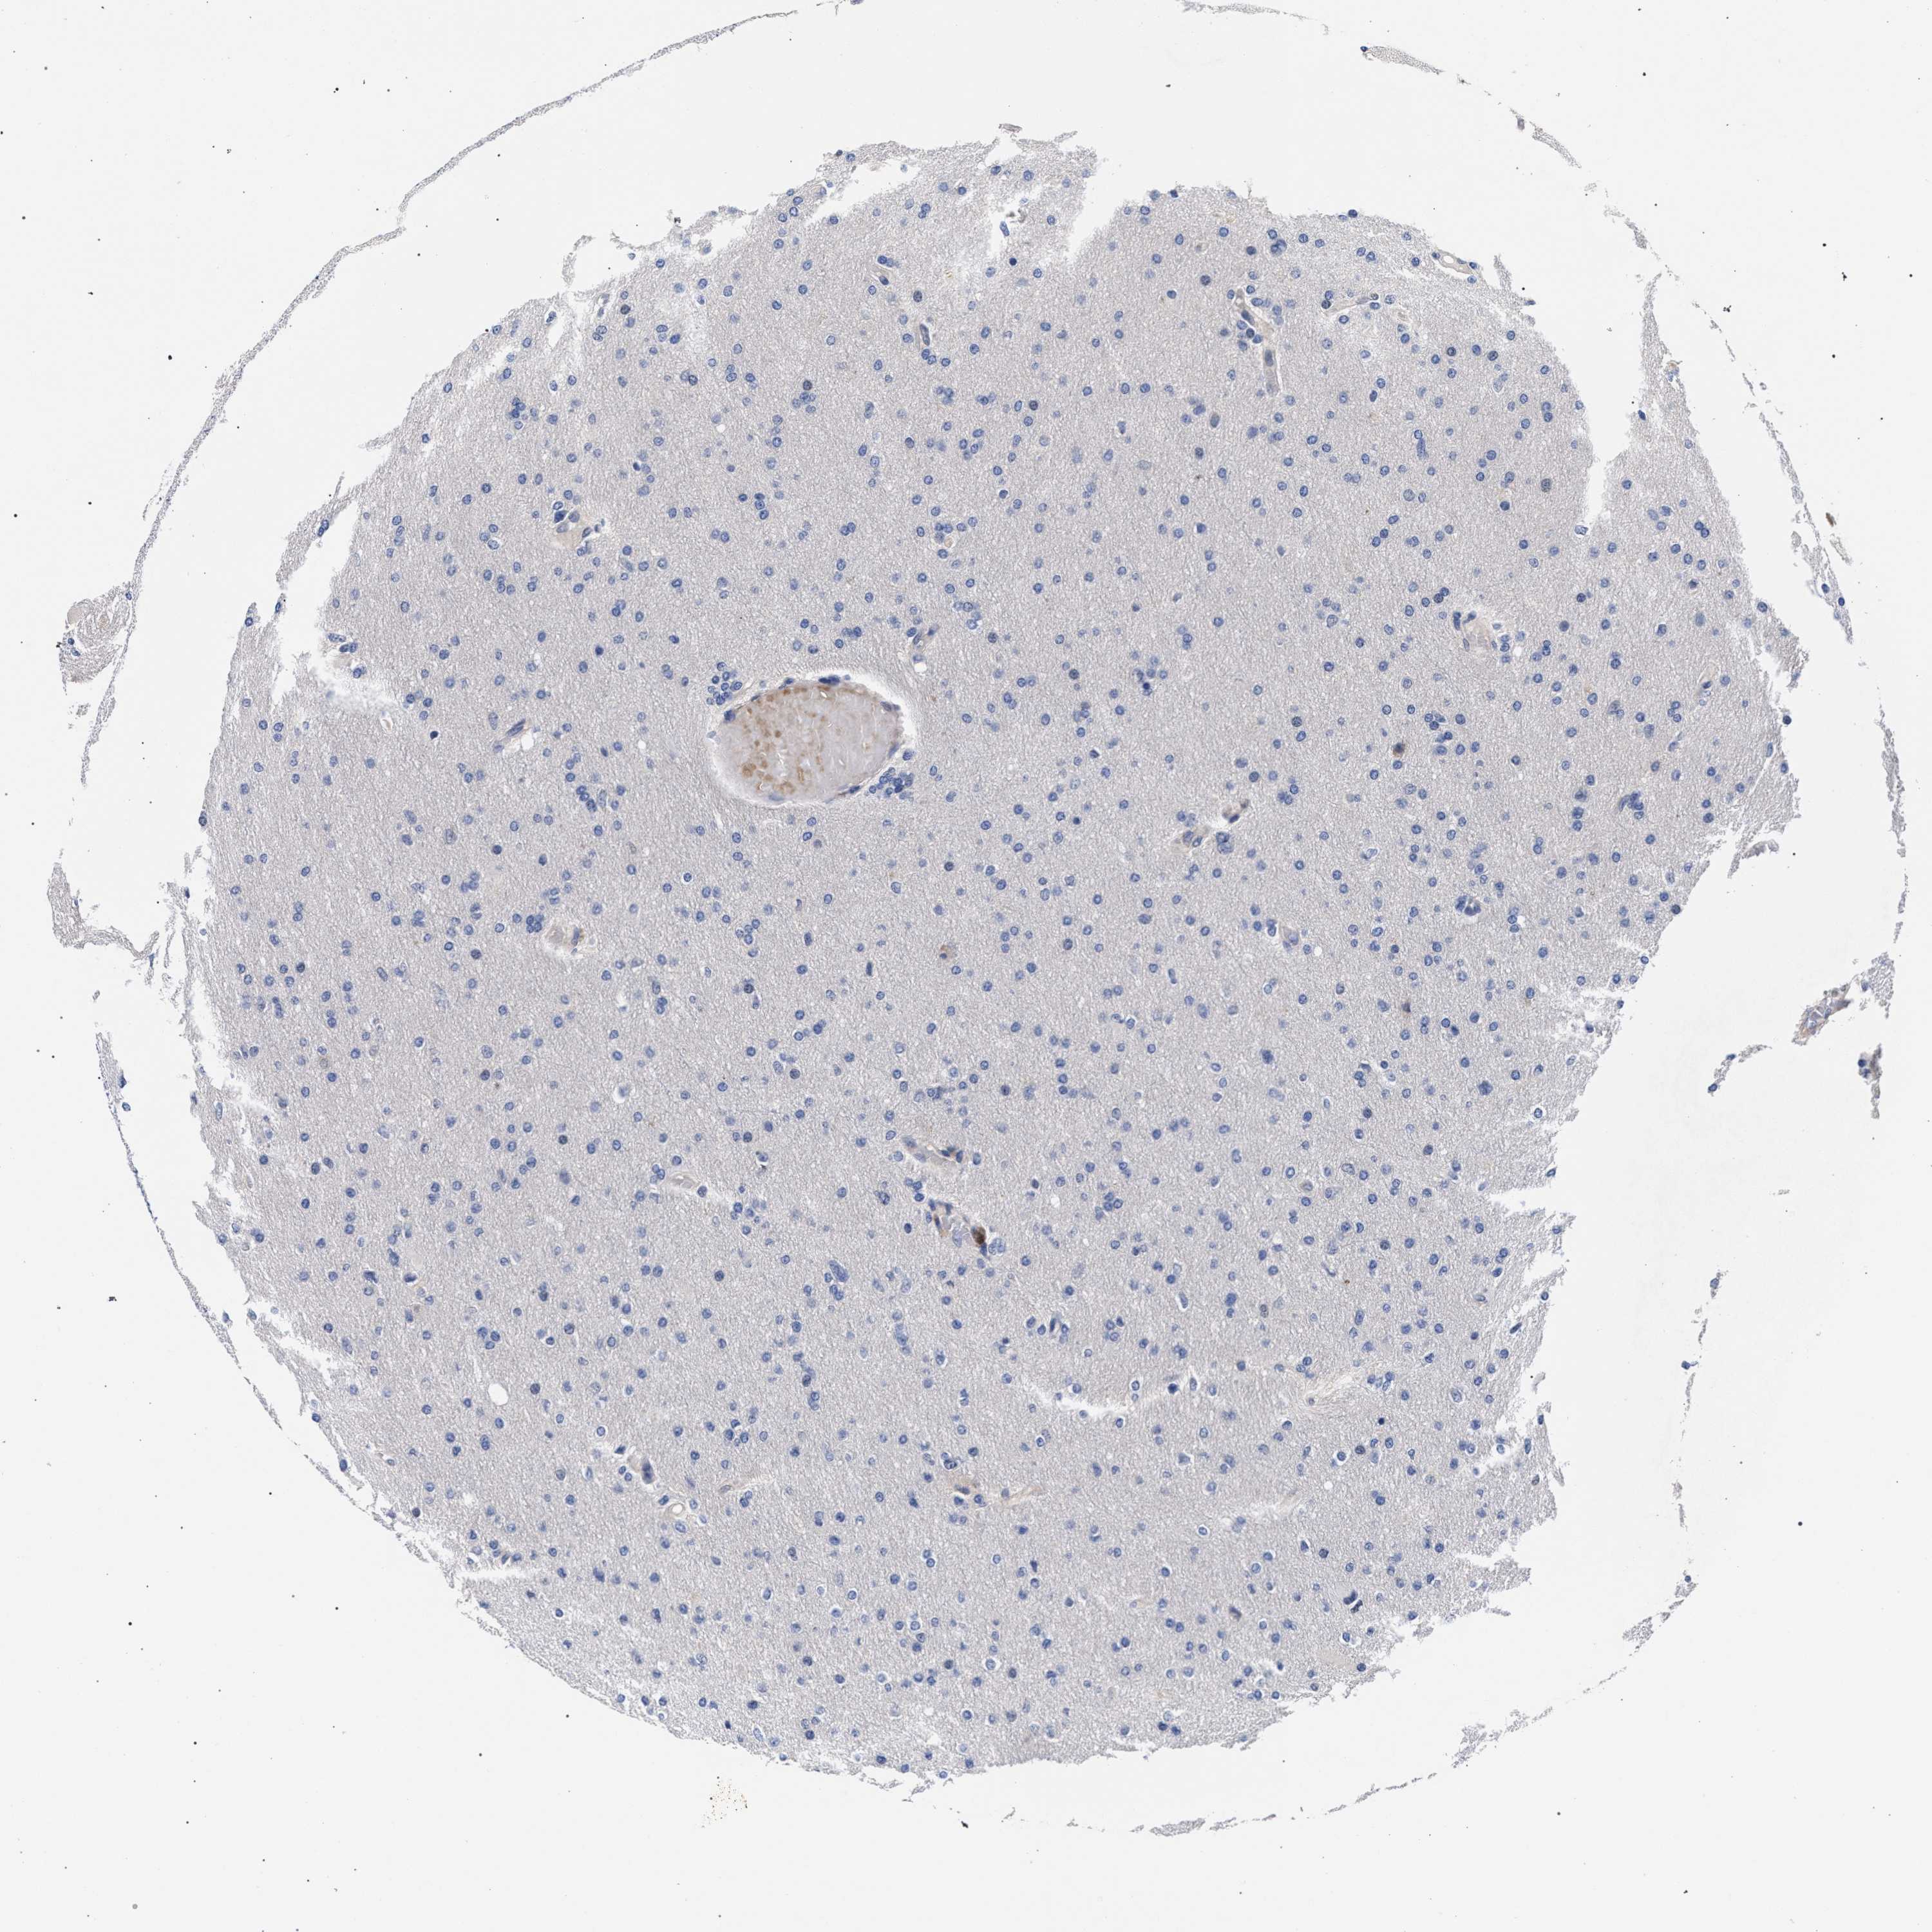

GLIOMA - Protein expressioni

A mouse-over function shows sample information and annotation data. Click on an image to view it in a full screen mode. Samples can be filtered based on level of antibody staining by selecting one or several of the following categories: high, medium, low and not detected. The assay and annotation is described here.

Note that samples used for immunohistochemistry by the Human Protein Atlas do not correspond to samples in the TCGA dataset.

Antibody stainingi

Antibody staining in the annotated cell types in the current human tissue is reported as not detected, low, medium, or high, based on conventional immunohistochemistry profiling in selected tissues. This score is based on the combination of the staining intensity and fraction of stained cells.

Each image is clickable and will lead to virtual microscopy that enables deeper exploration of all samples and also displays staining intensity scores, fraction scores and subcellular localization as well as patient and tissue information for each sample.

Antibody HPA019232

Antibody HPA021497

Antibody HPA021768

Staining

High

Medium

Low

Not detected

Intensity

Strong

Moderate

Weak

Negative

Quantity

>75%

75%-25%

<25%

None

Location

Nuclear

Cytoplasmic/membranous

Cytoplasmic/membranous,nuclear

Glioma, malignant, High grade

Glioma, malignant, Low grade